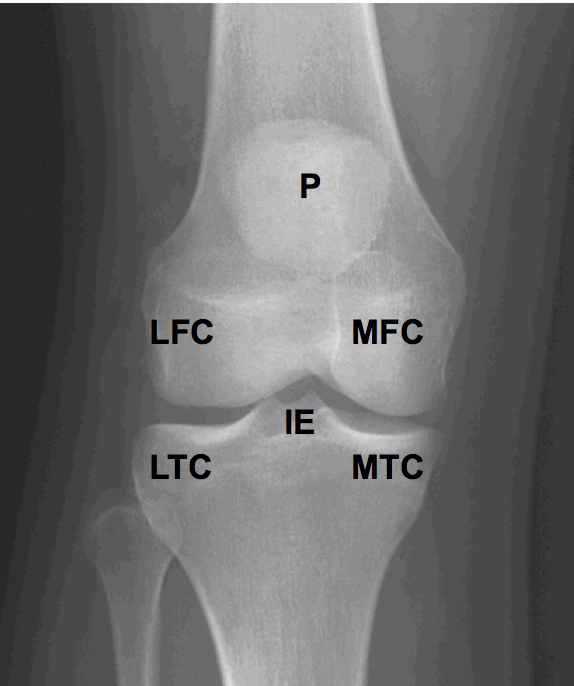

Articulation of the knee joint is between:

Label: